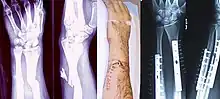

A bone fracture (abbreviated FRX or Fx, Fx, or #) is a medical condition in which there is a partial or complete break in the continuity of any bone in the body. In more severe cases, the bone may be broken into several fragments, known as a comminuted fracture.[1] An open fracture (or compound fracture) is a bone fracture where the broken bone breaks through the skin.[2]

Treatment of bone fractures are broadly classified as surgical or conservative, the latter basically referring to any non-surgical procedure, such as pain management, immobilization or other non-surgical stabilization. A similar classification is open versus closed treatment, in which open treatment refers to any treatment in which the fracture site is opened surgically, regardless of whether the fracture is an open or closed fracture.[38]

Since bone healing is a natural process that will occur most often, fracture treatment aims to ensure the best possible function of the injured part after healing. Bone fractures typically are treated by restoring the fractured pieces of bone to their natural positions (if necessary), and maintaining those positions while the bone heals. Often, aligning the bone, called reduction, in a good position and verifying the improved alignment with an X-ray is all that is needed. This process is extremely painful without anaesthesia, about as painful as breaking the bone itself. To this end, a fractured limb usually is immobilized with a plaster or fibreglass cast or splint that holds the bones in position and immobilizes the joints above and below the fracture.

When the initial post-fracture oedema or swelling goes down, the fracture may be placed in a removable brace or orthosis. If being treated with surgery, surgical nails, screws, plates, and wires are used to hold the fractured bone together more directly. Alternatively, fractured bones may be treated by the Ilizarov method which is a form of an external fixator.